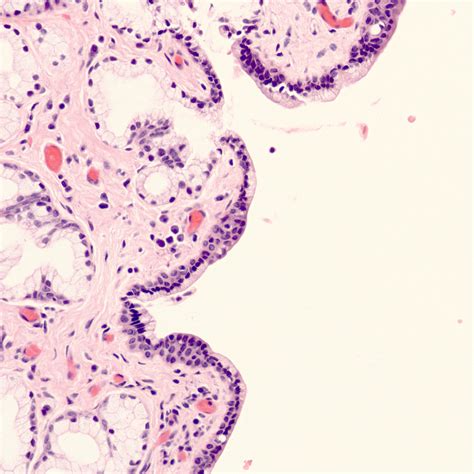

• Epithelial Inclusion: During healing, epithelial cells may become trapped beneath the surface of the vaginal wall, leading to the development of a cyst.

• Biopsy: In some cases, a biopsy may be performed to rule out other conditions, such as cancer.